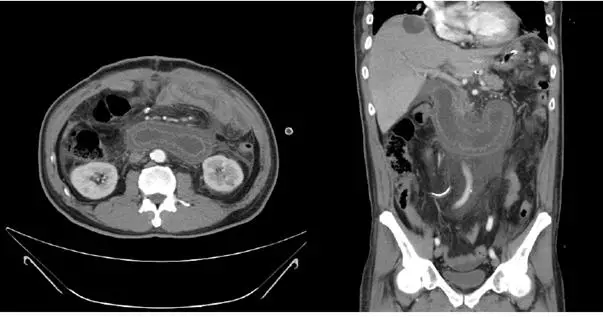

本題使用與上題相同的電腦斷層影像(軸切面 + 冠狀切面),用以支持治療決策。

影像重點回顧:

- 右上腹可見巨大液體充填(fluid-filled)管腔,形成 C-loop sign,圍繞胰臟頭部,管壁可見 keyboard sign(valvulae conniventes)

- 管腔極度擴張,估計直徑 ≥ 5 cm,充滿膽汁及胰液

- 無游離腹腔氣體(free air),尚未見明顯穿孔跡象

- 腸壁強化尚存(無明顯缺血壞死的 CT 早期徵象)

治療決策意涵: CT 顯示急性完全性阻塞,輸入腸端高度擴張,若不處理,腸壁壓力持續升高將導致缺血壞死與穿孔。此影像直接支持需要手術介入的判斷。